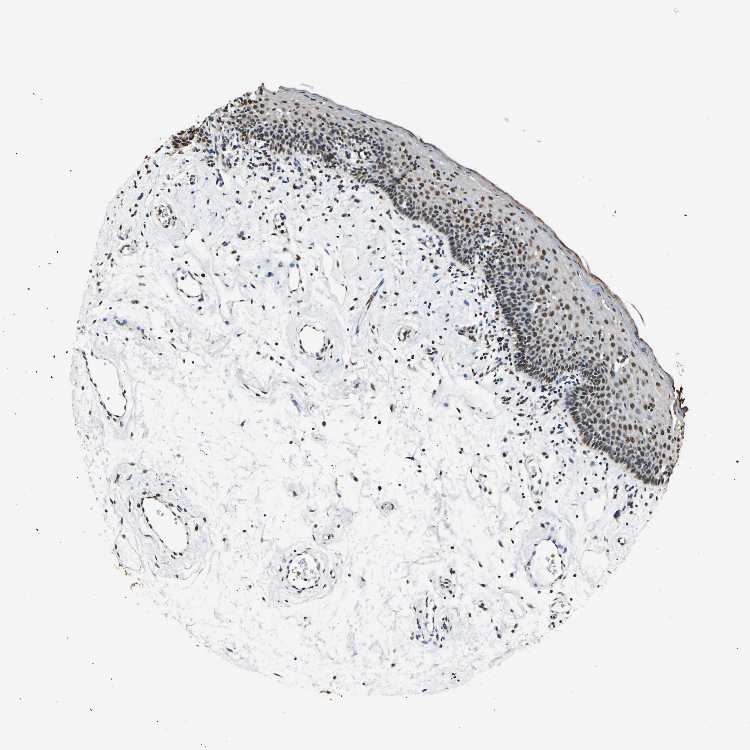

TISSUE PRIMARY DATA ORAL MUCOSA Show tissue menu

ORAL MUCOSA - Antibody stainingi

Antibody staining in the annotated cell types in the current human tissue is reported as not detected, low, medium, or high, based on conventional immunohistochemistry profiling in selected tissues. This score is based on the combination of the staining intensity and fraction of stained cells.

Each image is clickable and will lead to virtual microscopy that enables deeper exploration of all samples and also displays staining intensity scores, fraction scores and subcellular localization as well as patient and tissue information for each sample.

Antibody HPA016832Antibody HPA020076Antibody CAB001969

Squamous epithelial cells HighHighHigh